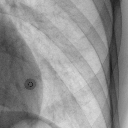

右肺下野钙化灶(12.66MB)

右肺下野钙化灶